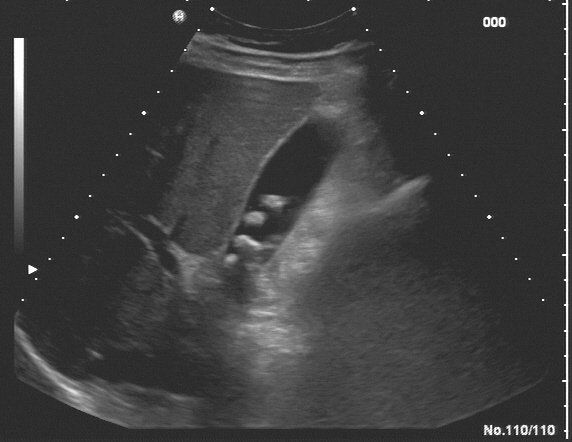

Sonographie des Abdomens

Mit der Ultraschalluntersuchung des Abdomens können die Organe des Bauchraums untersucht werden. Der Schallkopf sendet Ultraschallwellen aus, diese werden je nach Konsistenz des Gewebes absorbiert oder reflektiert. Der Schallkopf empfängt die reflektierten Wellen und wandelt diese in elektrische Impulse um, welche auf dem Bildschirm dargestellt werden. Diese Bilder zeigen Größe, Form und Struktur der untersuchten Organe. Die Beurteilbarkeit ist individuell unterschiedlich und kann durch Übergewicht und Luft im Magen-Darmtrakt beeinträchtigt sein. Besonders geeignet ist die Sonographie zur Feststellung von Erkrankungen der Leber, Nieren, Gallengängen und Bauchspeicheldrüse. Bezüglich Magen und Dickdarm ist die Gastroskopie bzw. Koloskopie überlegen.

Wenn die Untersuchung am Vormittag stattfindet, sollten Sie ganz nüchtern sein (Ihre Medikamente dürfen Sie einnehmen). Bei Untersuchungen am Nachmittag dürfen Sie frühstücken. Ansonsten ist keine spezielle Vorbereitung notwendig.